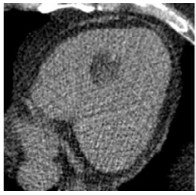

入院后签署患者知情同意告知书,查血常规、凝血谱、电解质、血生化、甲状腺功能、肿瘤标志物、C反应蛋白和脑钠肽均未见明显异常,心电图示窦性心律,顺钟向转位。连续心电遥控监护5 d未见明显室性心律失常。心脏超声和经食道心脏超声检查提示室间隔及左室下壁中段近后内侧乳头肌处可见一个偏高回声区,主要位于心肌内,浸润心肌全层,部分凸向左室腔,略见活动及变形,未累及二尖瓣和主动脉瓣,未见心腔流入道和流出道梗阻,未见明显心包积液。左心声学造影显示室间隔中下段偏强回声团块内未见明显血流信号,乏血供表现。心脏多层螺旋计算机断层扫描(CT)示室间隔内异常密度,测其CT值为-31.3 Hu,提示为脂肪组织密度,增强后病灶未见强化,诊断为脂肪来源肿瘤,脂肪瘤考虑(图 1~2)。心脏磁共振(CMRI)增强扫描示FIESTA序列显示后室间隔-左室下壁见一混杂高信号“小核桃”样大小肿物,T2WI(图 3)上为高信号,Triple IR序列(图 4)上病灶全部为低信号,提示为纯脂肪成分,病变周围可见低信号环,提示为化学位移伪影,病变质地较软,边界尚清楚,电影序列可见病灶柔软摆动,并随心动周期形态改变,局部突入左心室,舒张末期测量大小约25 mm×19 mm×36 mm,灌注序列见灌注确实,延迟增强未见强化,拟诊为心脏脂肪瘤(图 5)。SPECT心肌静息灌注显像见室间隔和左室下壁局部心肌血流灌注减低。18F-FDG PET-CT显像提示室间隔-左室下壁心肌内病变糖代谢减低,考虑为脂肪源性病变,全身未见局部异常密度增高。

| 图 3 心脏磁共振图 |

当发现存在心脏肿瘤时,首先需要明确其性质,尤其是良恶性。CT和磁共振对脂肪瘤的识别具有高度特异性[12-13],本患者CT检查示室间隔脂肪组织均匀低密度影。MR清晰显示肿瘤边界,T1W1呈强信号,T2W1呈稍强信号,脂肪组织序列呈弱信号,钆增强后也未见明显强化,对映证脂肪瘤均有较大价值。患者肿瘤的CT值同皮下脂肪组织,同时结合心超等其他影像学依据可排除黏液样变、血管组织、肌肉组织、纤维组织和错构瘤等其他组织来源,因此可临床确诊为脂肪来源的肿瘤。肿瘤形态、血供是否丰富和代谢是否活跃是鉴别脂肪瘤和脂肪肉瘤的重要依据。超声、CT和磁共振均提示肿瘤为单个,与周围组织边界清楚。患者接受了超声左心声学造影和核素心肌静息灌注显像检查,均提示肿瘤血供明显不丰富。18F-FDG PET-CT检查显示肿瘤放射性摄取呈稀疏缺损区,提示葡萄糖代谢减低,符合良性肿瘤表现,同时也未见全身其余部位有高糖代谢病灶,因此临床诊断良性脂肪瘤成立。2011年AECVP/SCVP心内膜心肌活检共识声明认为对左心系统肿瘤无需进一步进行心肌活检[7]。